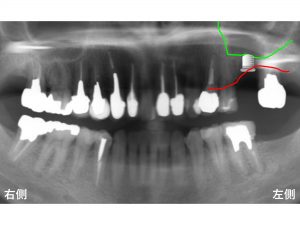

わかりやすいように骨吸収の状態を線でかいて見ます。

以下の青線が骨吸収する前の元々の骨の位置です。

現在の骨吸収した状態が以下の赤線です。

そして緑線が上顎洞の一番下の部分です。

この3つの線を組み合わせたのが以下です。

現在のように骨吸収している場合には、

インプラント治療が困難となります。